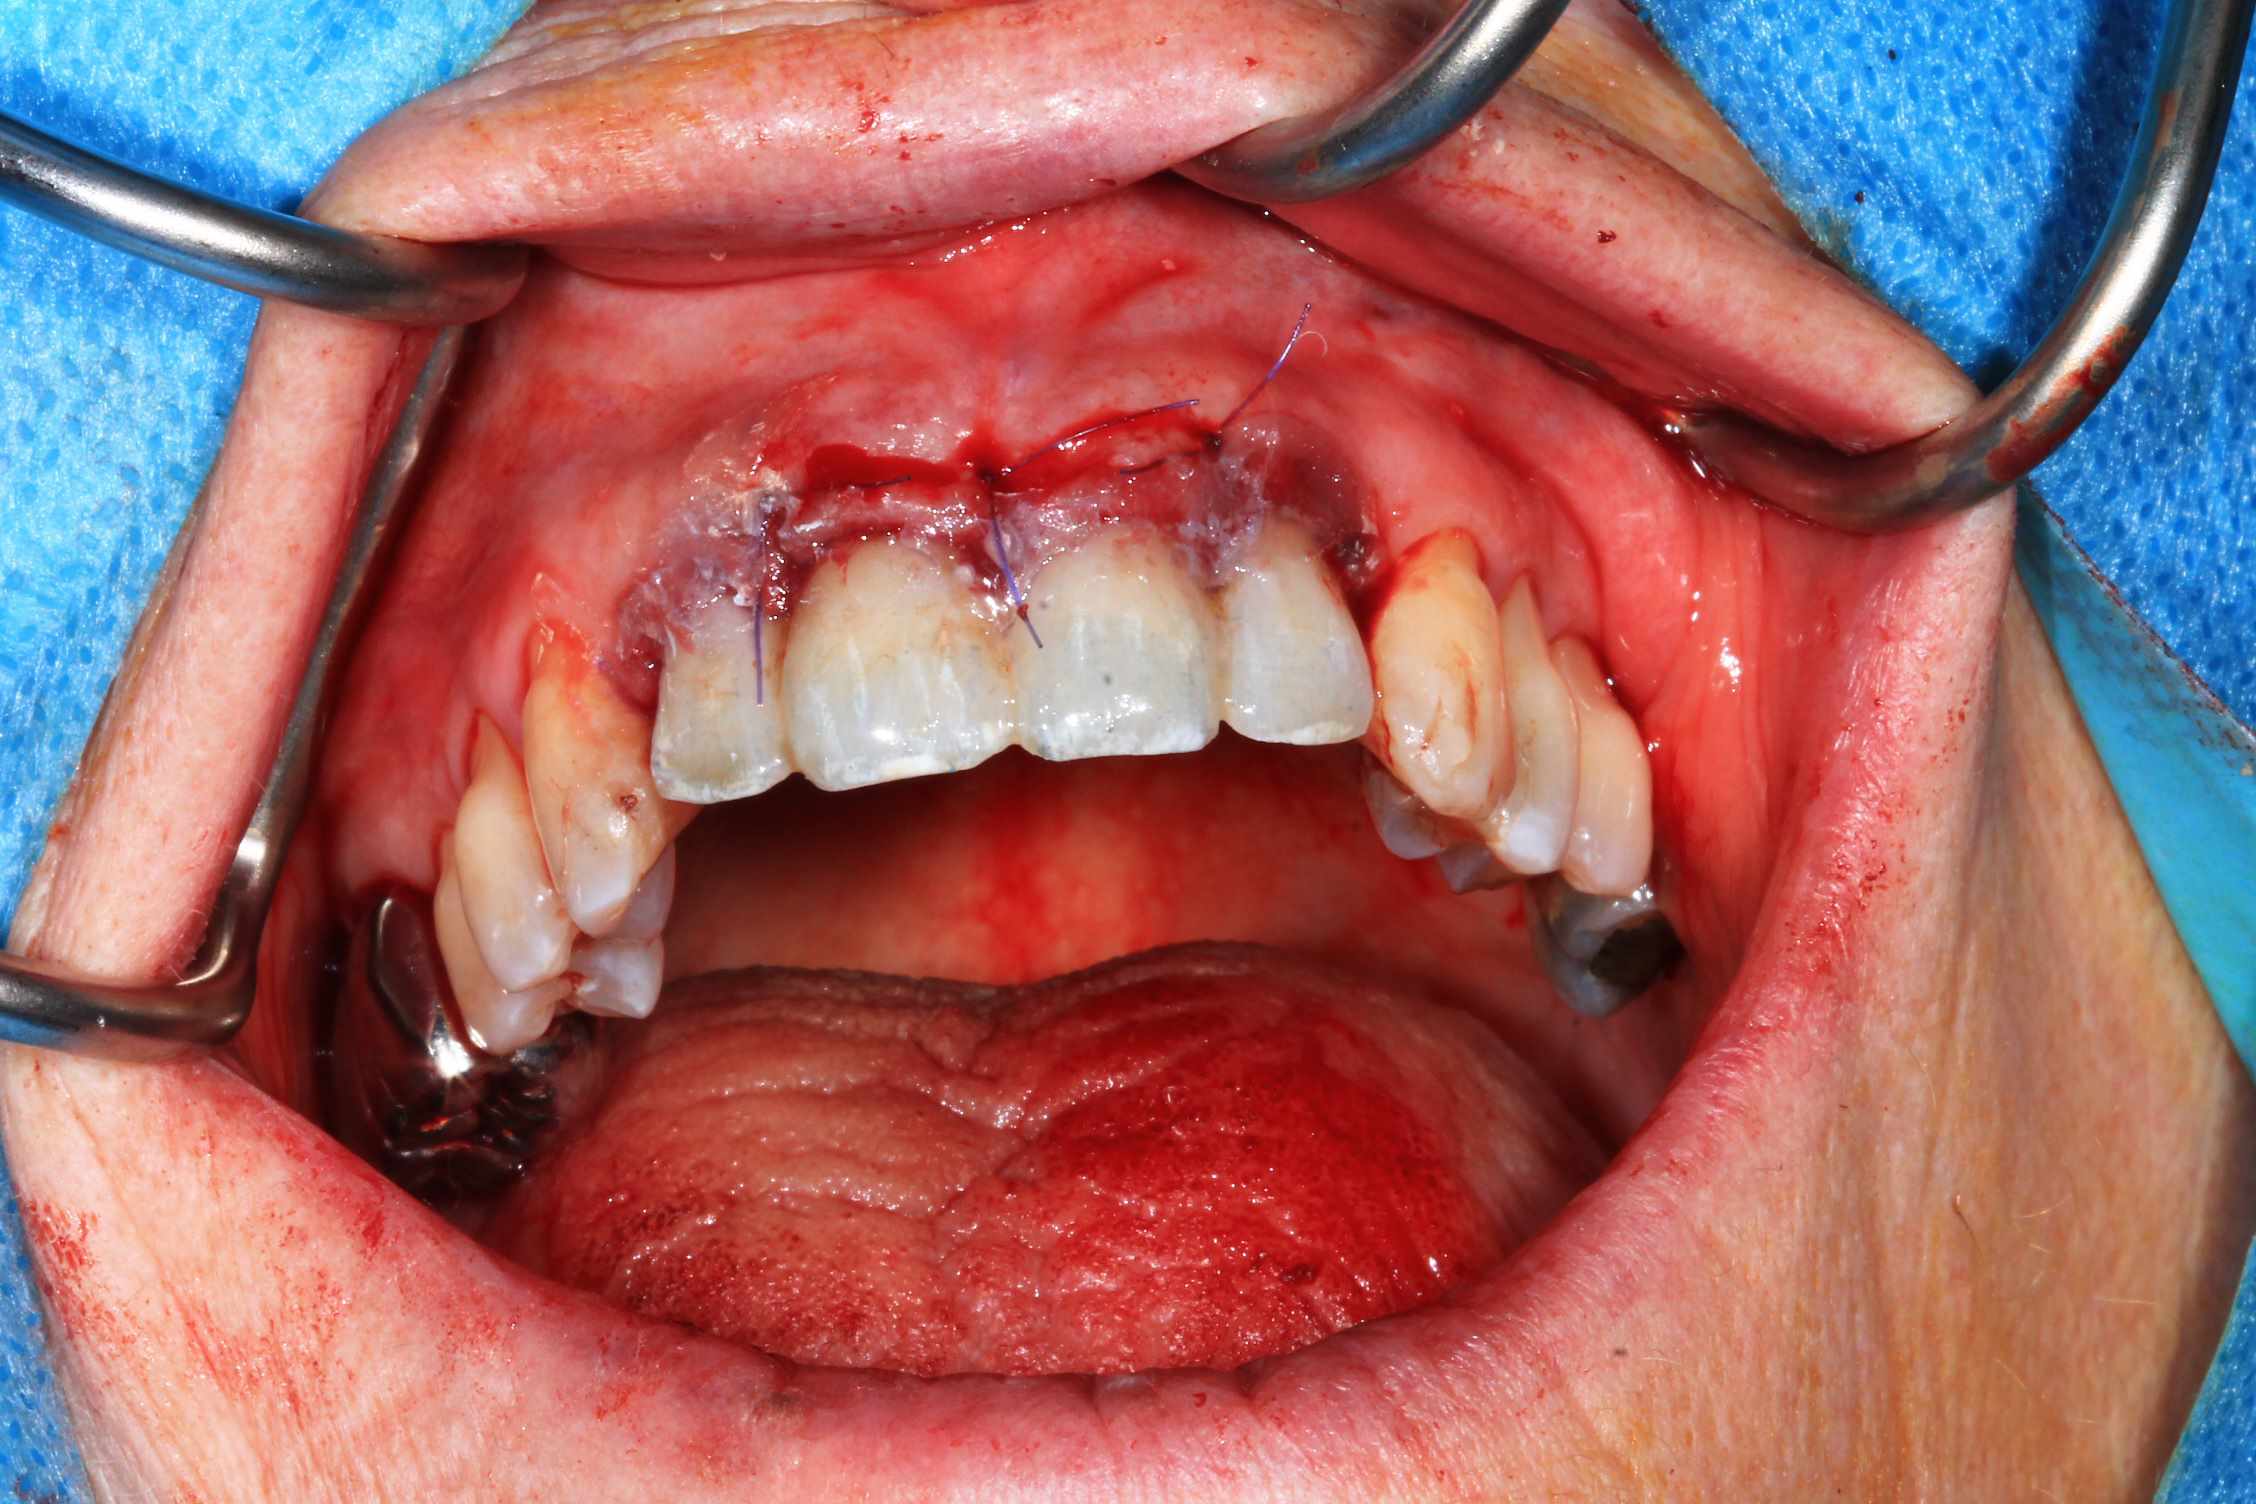

Chir : extraction, implant flapless et pose du bridge imprimé Flexera rosenscrew.

Oo2hlrfz7899rhfapzhptk1dqg77 - Eugenol

57n0uy1188a85maq093dyeqfkqlh - Eugenol

Ujfw7wykxh3fhbwxszqf740ci3rt - Eugenol

S7tplsv5ffydeo8n22bhttsnmndc - Eugenol